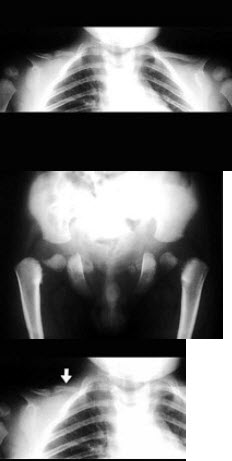

188、单项选择题

男,8岁,易疲劳,活动后心悸、气急,结合图像,最可能的诊断是()

A.房间隔缺损

B.室间隔缺损

C.肺动脉狭窄

D.动脉导管未闭

E.法洛氏四联症

点击查看答案